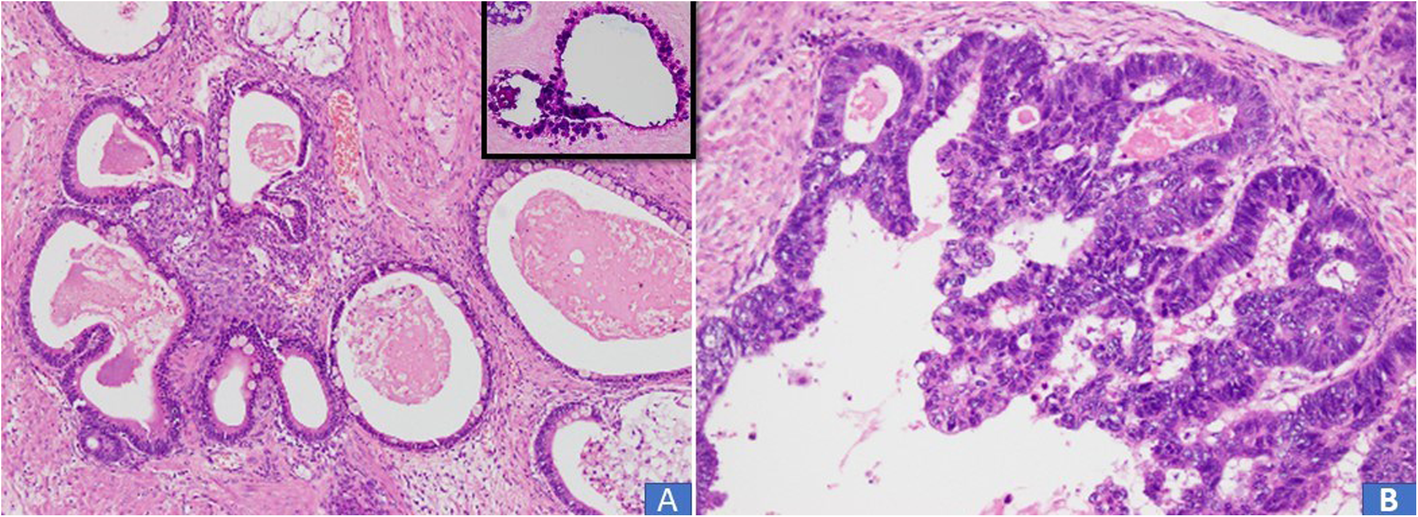

Fig. 5

Seromucinous carcinoma recategorized as endometrioid adenocarcinoma with mucinous differentiation. a Variably dilated glands lined by columnar epithelium with mucinous cytoplasm. (Inset) PAS special stain depicting cytoplasmic mucin. b In other areas, high grade tumor was noted with cribriform pattern and pleomorphic columnar lining cells